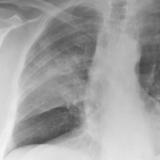

Pancoast

Album: Pancoast

Date: 03/03/2004

Size: 19 items

Views: 38876